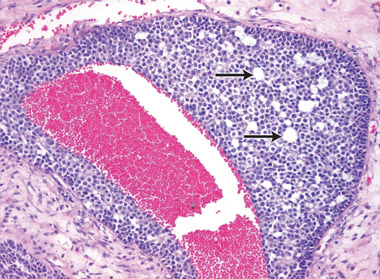

At 59 years of age, a laparotomy was performed and the patient was found to have a large left adnexal mass (Box 1, A) and a normally formed uterus. The mass was removed and a subtotal hysterectomy performed as there was no distinct lower margin of the cervix (Box 1, B). The patient was informed of the operative findings and the diagnosis of intersex. Peripheral blood karyotyping showed a 46,XY genotype. The histopathology of the gonadal tumour showed a sex cord-stromal tumour of indeterminate differentiation (Box 2). The histopathology of the uterus showed simple endometrial hyperplasia. The patient was treated with postoperative chemotherapy, but died 18 months later.

The risk of malignancy in dysgenetic gonads is significantly increased in some patients with DSD.8 The presence of the SPY gene on the GBY region of the Y chromosome is a prerequisite for malignant transformation.9 Tumours can arise in any of the gonadal cells or their precursors.8 Precursor lesions for the development of cancers occur as carcinoma-in-situ in testicular tissue and gonadoblastoma in undifferentiated gonadal tissue. A number of malignant tumour types may occur in dysgenetic gonads.8,10 These include germ cell tumours and sex cord-stromal tumours. Patients presenting with abdominal tumours in dysgenetic gonads in adulthood provide histopathologists with complex diagnostic dilemmas. Histopathological examination of the tumour in our case showed mixed elements, with cells resembling ovarian follicles, testicular tunica, granulosa cells, Sertoli cells and Leydig cells. No germ cell components were identified. The final consensus was a diagnosis of malignant sex cord-stromal tumour of indeterminate differentiation.